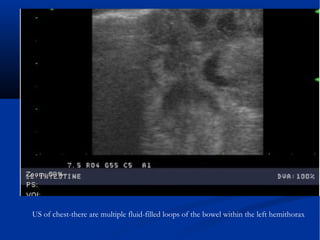

US of chest-there are multiple fluid-filled loops of the bowel within the left hemithorax

US of chest-thereare multiple fluid-filled loops of the bowel within the left hemithorax